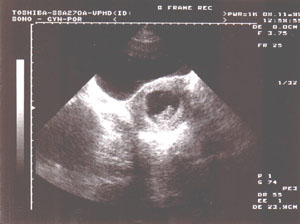

Tak jsem podstoupila ultrazvukové vyšetření, jako obvykle jsem se dozvěděla, že mám dělohu dozadu a pak pan doktor otočil monitor, abych na něj také viděla. Ukázal mi tam "něco", co vypadalo jako fazole a bude to naše miminko! :)))) Až nyní jsem uvěřila, že se uvnitř mě opravdu vytváří nový človíček! Poprosila jsem o fotičku (za 40,- Kč, ale kdo by nezaplatil?), a tak máme první foto našeho broučka. V celé jeho kráse ho na té fotce taky můžete vidět. To bylo 8.11.1999 a měřil 26 mm. A ještě jedna důležitá informace, viděli jsme 1 plod, tudíž dvojčata nebudou.